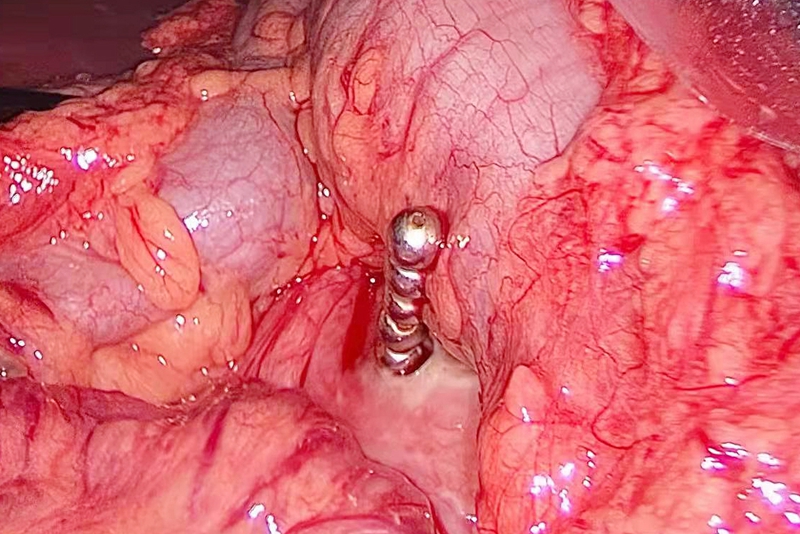

术中,通过微创腹腔镜探查,医生在患者胃内陆续探查到20颗磁力珠。

其中在胃大弯后壁,发现有5颗磁力珠已经突破胃壁进入腹腔,不仅造成胃穿孔,还引发肠壁充血水肿。于是,在取出磁力珠后,又进行了胃穿孔修补术。

“磁力珠磁性很强,太用力分离,反而可能加重肠壁损伤。”整场手术耗时两个多小时,才顺利完成。